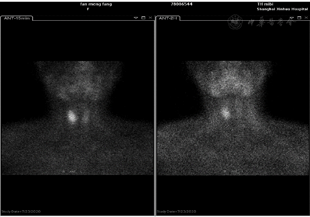

影像检查:颈部超声:右侧甲状腺背部实质性肿块。胸部CT:右肺下叶多发微小结节。腹部增强CT:胰腺尾部结节,结合病史考虑功能性腺瘤;双肾旋转不良,左侧为甚;回盲部多发稍大淋巴结(图1)。胃镜:反流性食管炎(LA-A),糜烂性胃窦炎。甲状旁腺ECT:右叶甲状腺中上极后部类圆形低密度肿块,提示甲状旁腺腺瘤可能(图2)。心电图、心脏超声、腹部超声均未见异常。

患者腹部增强CT示功能性腺瘤,实验室检查示血钙2.71 mmol/L;颈部超声示右侧颈部甲状腺背部实质性肿块,甲状旁腺ECT提示甲状旁腺腺瘤可能;基因检测结果提示Menin基因突变,MEN1诊断明确。患者及其父亲、妹妹的MEN1基因突变(同一杂合变异),目前发现妹妹血钙及PTH高于正常,但没有不适症状,无低血糖表现。